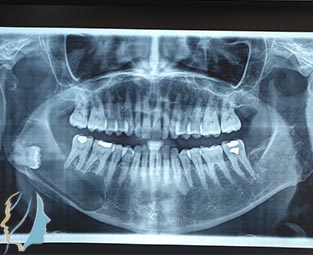

Πρόκειται για χειρουργική αφαίρεση οστεολυτικών βλαβών των γνάθων κατόπιν ανάλογου ακτινολογικού ελέγχου. Συνήθως περιλαμβάνουν και εκτομή τμήματος της ρίζας του υπεύθυνου δοντιού, τη γνωστή ακροριζεκτομή.

Τα συμπτώματα που υποδεικνύουν την ύπαρξη κύστικής βλάβης στη γνάθο είναι: Οίδημα (πρήξιμο) στην περιοχή των ριζών των δοντιών εμφανές ή όχι έξω από το στόμα, Έντονος πόνος στην περιοχή των ριζών των δοντιών, Κινητικότητα των δοντιών. Σε αρκετές περιπτώσεις τυχαίος ακτινολογικός έλεγχος μπορεί να αποκαλύψει την ύπαρξη ακόμη και ευμεγέθους κυστικής βλάβης στις γνάθους.